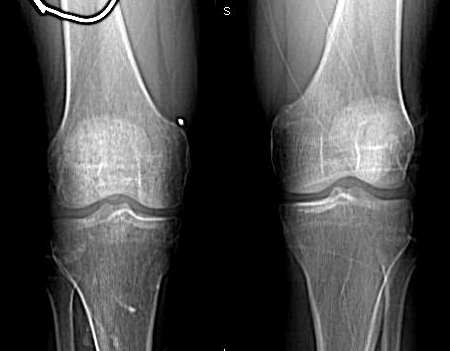

患者,男.40y,右侧膝关节疼痛半年,加重月余

右侧股骨下端 胫骨近端及髌骨见骨质疏松,松质及皮质见虫蚀状溶骨性破坏,皮质变薄,骨小梁减少模糊,胫骨近侧干骺端内侧骨破坏性,关节肿胀,关节间隙增宽,周围未见明显软组织肿块.

临床 右膝关节痛半年,加重月余